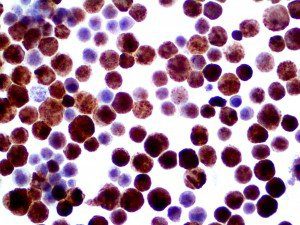

It is the ICU physician who is most likely to witness one of the deadliest manifestations of the abnormal immunological response, the cytokine storm syndrome (CSS). This response is also referred to by some as the cytokine release syndrome (CRS). CSS is characterized by continuous activation and expansion of macrophage and lymphocyte populations, which secrete large amounts of cytokines, causing the cytokine storm. This massive cytokine release is akin to hemophagocytic lymphohistiocytosis (HLH) disease, a syndrome characterized by initial unchecked and persistent activation of cytotoxic T lymphocytes and NK cells.

Clinical and laboratory manifestations of HLH include fever, enlarged liver and/or spleen, neurologic dysfunction, coagulopathy, liver dysfunction, cytopenias (i.e., low levels of erythrocytes, leukocytes, and/or platelets), hypertriglyceridemia, hyperferritinemia, hemophagocytosis, and eventually diminished NK cell activity as the immune system becomes progressively paralyzed. HLH can be familial (primary HLH) or secondary to another disease process (sHLH), such as rheumatic disease, in which it is referred to as macrophage activation syndrome (MAS, characterized by elevated ferritin).